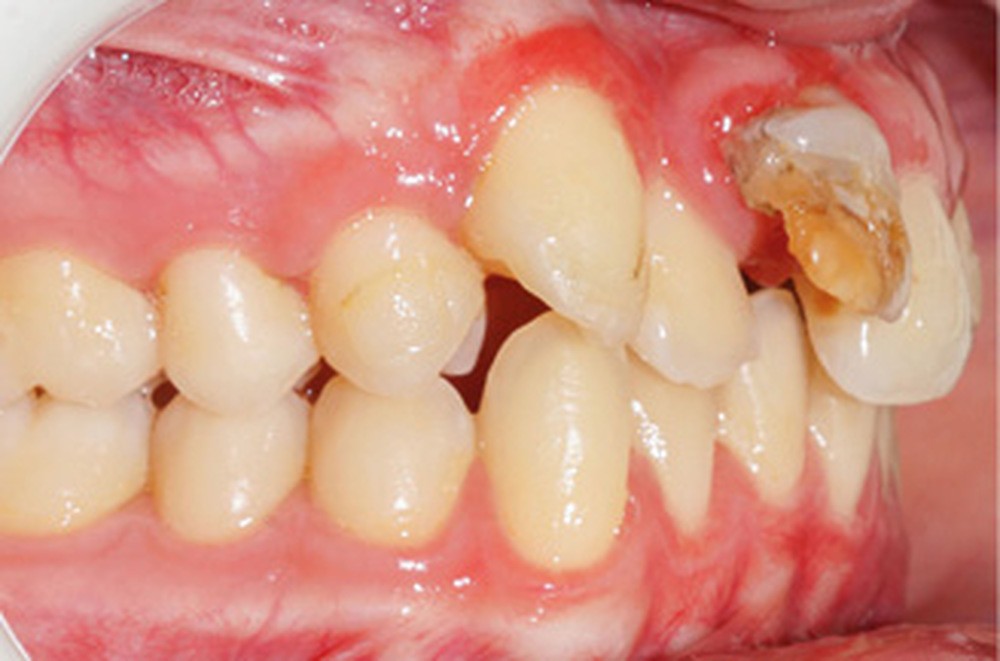

D’un point de vue occlusal, le patient, en denture adulte jeune stable, présente une classe II d’Angle bilatérale de 4 mm, associée à un encombrement maxillaire de 5 mm et mandibulaire de 2 mm. La face mésiale de 21 est centrée avec le plan sagittal médian, la non-concordance des médianes incisives est d’origine mandibulaire (déviation de la médiane mandibulaire vers la gauche) (fig. 1b-d).

Son incisive centrale supérieure droite (11) présente un défaut de structure amélaire sévère, compromettant une technique restaurative pérenne a minima. L’examen de la panoramique (fig. 1e) et de la radiographie rétroalvéolaire de 11 (fig. 1f) objective une fracture coronaire verticale, ainsi qu’une racine grêle et courbe, peut-être en rapport avec un ancien traumatisme [1]. Le rapport couronne clinique/racine clinique est défavorable.